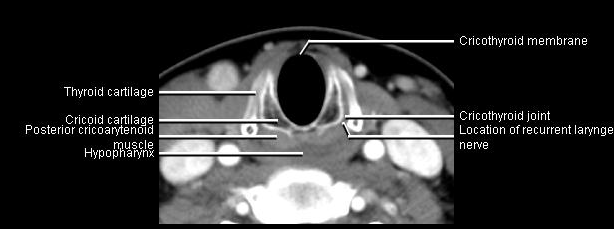

Phonation and dysphagia involve multiple coordinated structures in the larynx and pharynx. Radiation induced dysphagis appears to be related to dose to the phyaryngeal constrictor muscles and specific regions of the supraglottic and glottin larynyx.

Speech is impacted by doses to the epiglottis, base of tongue, aryepiglottic folds, false vocal cords upper esophageal sphincter and cricoid cartilage.

The mean laryngeal volume receiving > 50 Gy was a predictor of laryngeal edema. Vocal functions are usually well preserved with doses of 60 - 66 Gy. Dornfeld found a strong correlation between speech quality and dose to the ariepiglottic folds, pre-epiglottic space, false vocal cords and lateral pharyngeal walls at the level of the false vocal cords. A steep decrease in dose function was noted when doses exceeded 66 Gy.